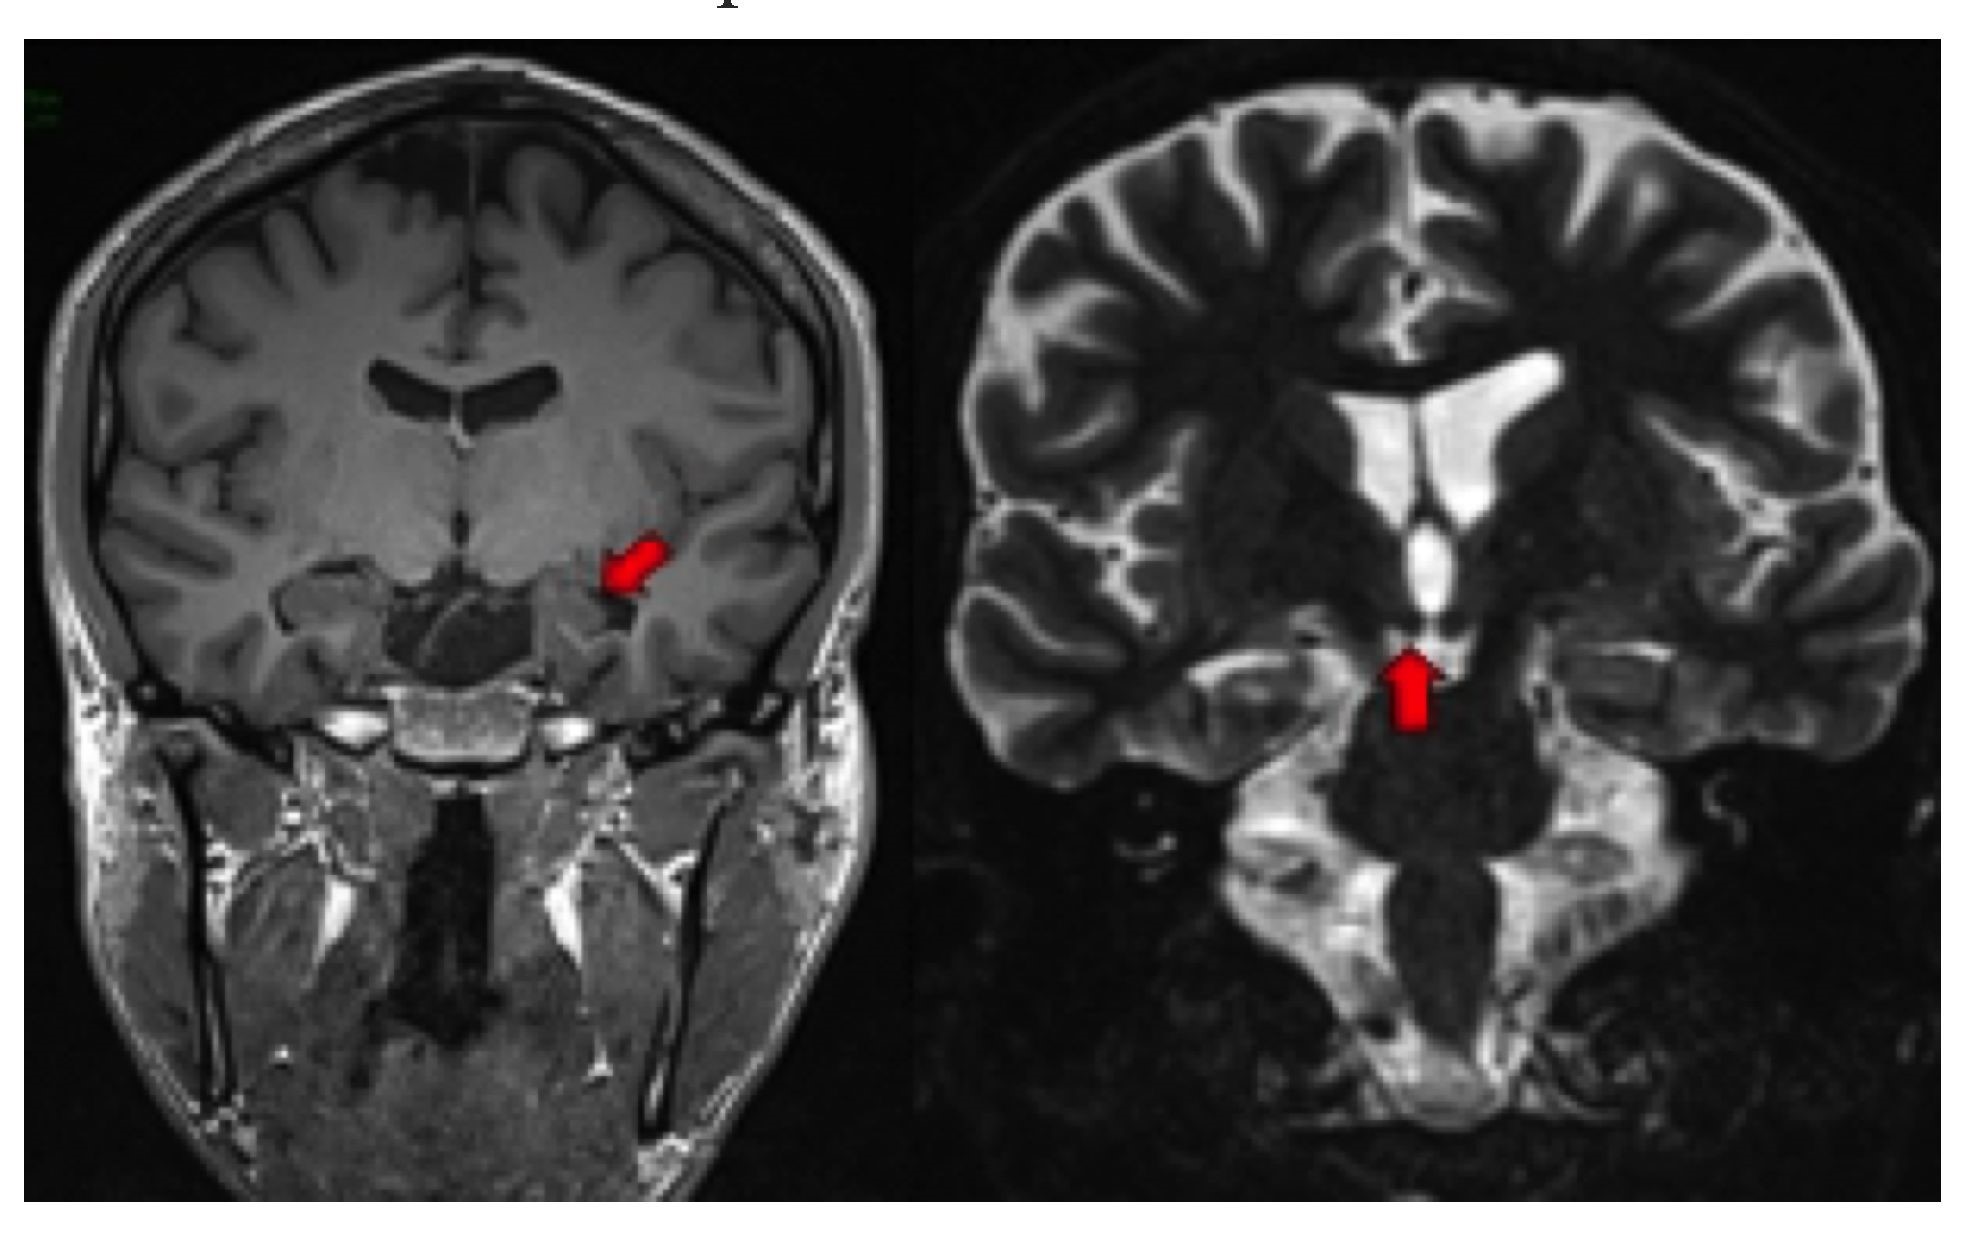

Los signos secundarios incluyen pérdida de la arquitectura interna del hipocampo, pérdida de las digitaciones de la cabeza del hipocampo que normalmente contiene dos o tres digitaciones (Figura 3izquierda), dilatación del asta temporal ipsilateral asociada a la atrofia hipocampal, aumento de la intensidad de señal de la amígdala, pérdida de volumen del lóbulo temporal (31), atrofia del cuerpo mamilar (Figura 3derecha), atrofia del fórnix(Figura 4), atrofia del tálamo y atrofia del giro del cíngulo, ipsilateral a la afectación hipocampal (32-34).